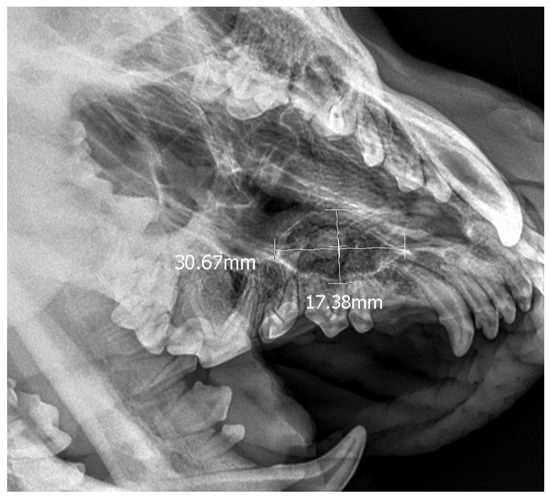

• Case 4

Figure 10. X-ray confirming the presence of an ectopic tooth along with a 3 cm × 1.7 cm dentigerous cyst on the left side.